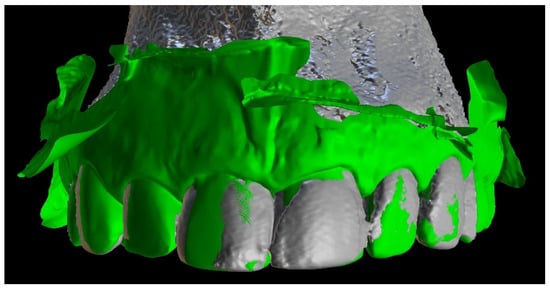

The next step was to align the DICOM and STL files to design a teeth-supported template (Figure 3).

Figure 3. Image presenting aligned files of patient’s CBCT data and intraoral scan.